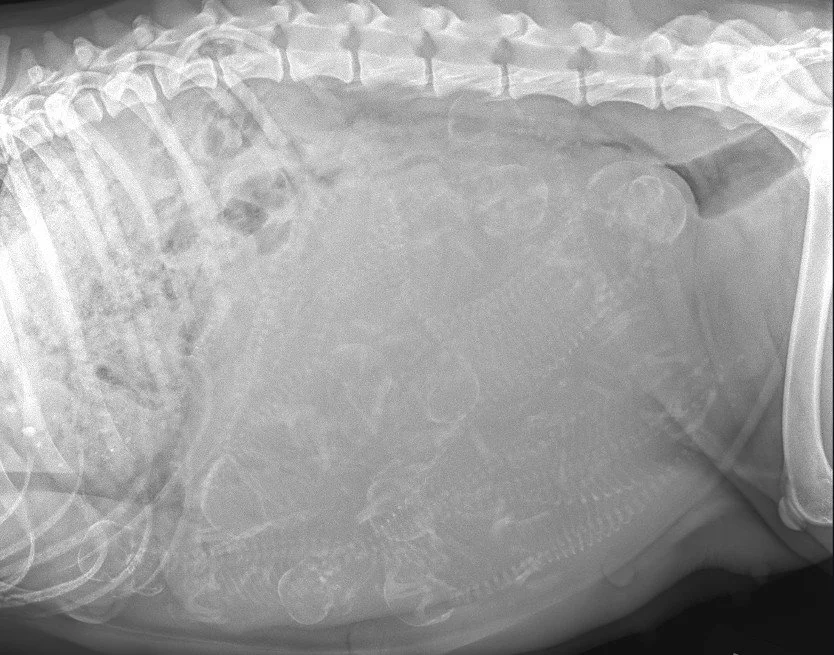

Sterling Veterinary Clinic has onsite digital x-ray, digital dental x-ray, and ultrasound capabilities to aid in diagnosing your pet’s disease or injury.